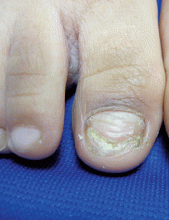

A 5-year-old boy presents to his physician for evaluation of "toenail issues" for at least 1 year. The family has noticed changes of the his right great toenail, which they thought might be due to "tight shoes," stating that the boy has been growing out of his shoes quickly. In the last 6 months, his mother has noted a "crumbly" nail with yellow discoloration. There has been no prior treatment, although his parents now are replacing his sneakers more regularly to allow him "room to grow." He has no history of toe swelling or pain. He is otherwise healthy, and he has no history of psoriasis or eczema. He has had no significant viral infections, although some children in his school did have hand, foot, and mouth disease several months ago. His mother states that her husband has athlete's foot, which has been treated with "creams and sprays." Physical exam The toenail of the right foot great toe has thickening of the distal part of the nail, with onycholysis (separation of the nail plate from the nail bed), yellow discoloration, and subungual debris. The right toe shows some chronic dystrophy. Other toenails appear normal, and the skin of the feet is otherwise unremarkable.